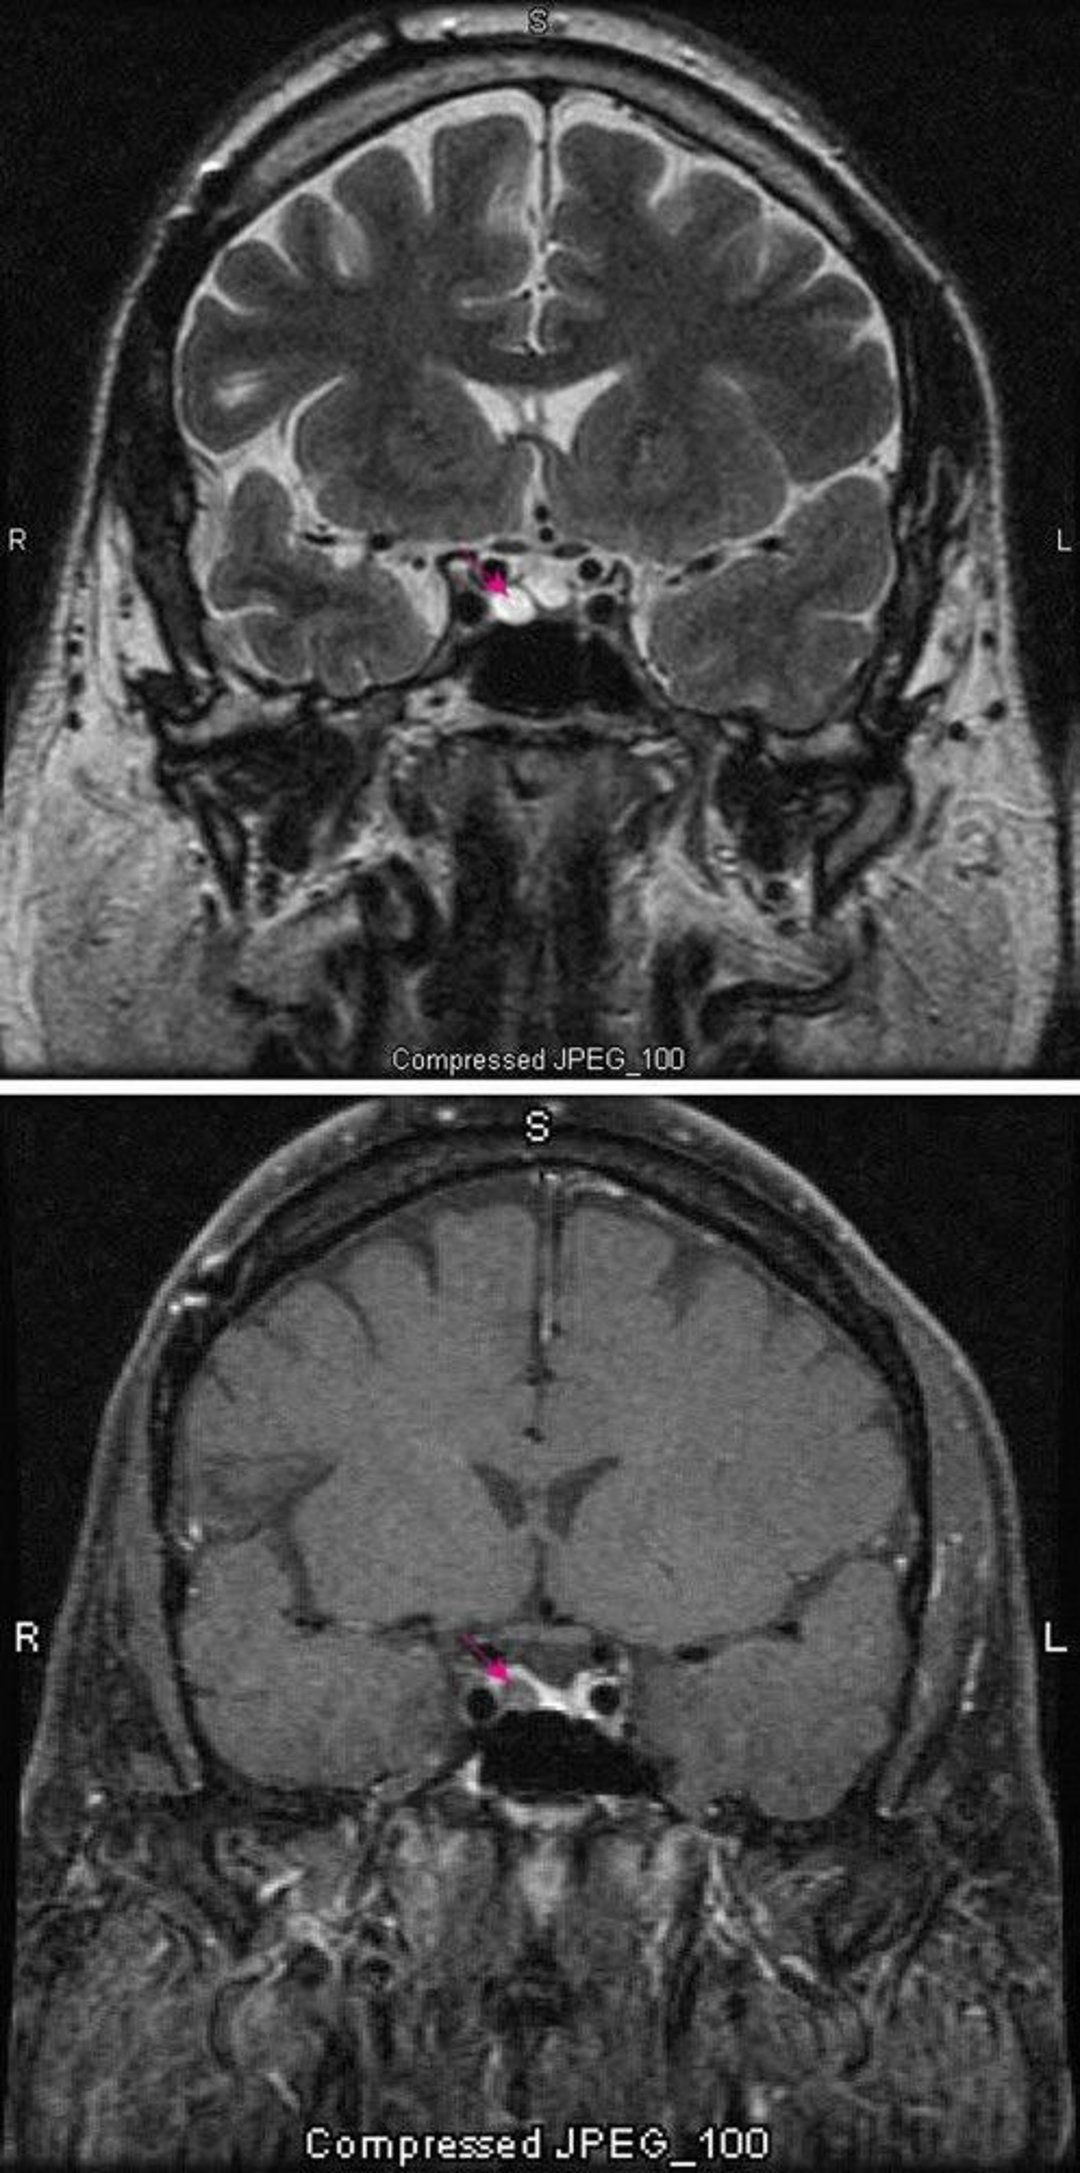

Pituitary Microadenoma

T2-weighted MRI scan (top) shows a pituitary microadenoma (red arrow). Contrast (bottom) normally enhances the pituitary (red arrow). The adenoma appears lighter.

Images courtesy of William R. Shapiro, MD.